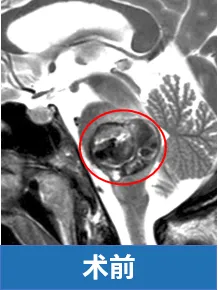

45岁的劳拉,突发脑干海绵状血管瘤出血,面瘫、偏瘫,躺在床上已经下不了床。到达医院时,情况已经很糟糕。

她眼睛通红,两侧眉毛一高一低,双眼也明显大小不一,面部歪斜。由于严重的吞咽功能障碍,她已无法经口进食,只能依赖鼻饲管维持营养。

但劳拉的这个海绵状血管瘤长在桥脑上,病变已经把桥脑撑的像个气球。

INC巴特朗菲教授(巴教授)在精细清除血肿及血管畸形的同时,特别注意保护脑桥后部实质及外展神经、面神经的完整性。

术后一年,明显可以看到劳拉的面神经和外展神经功能已基本恢复,面瘫不再,喜笑颜开。

上述真实案例及图片来自于INC巴特朗菲教授课程演讲。